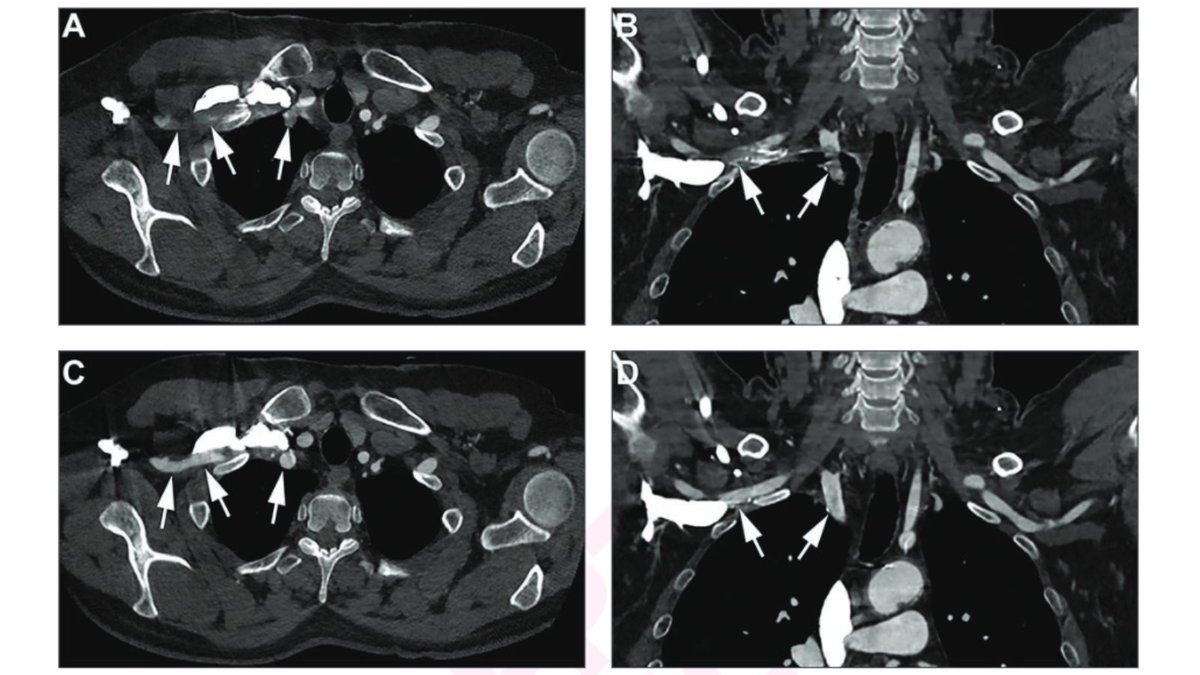

New AJR Accepted Manuscript: "Artifactual Subclavian Artery Thrombosis on CTA With Iterative Metal Artifact Reduction" By Drs Neubauer & Jan Vosshenrich, MD UniSpitalBaselCH ajronline.org/doi/10.2214/AJ…